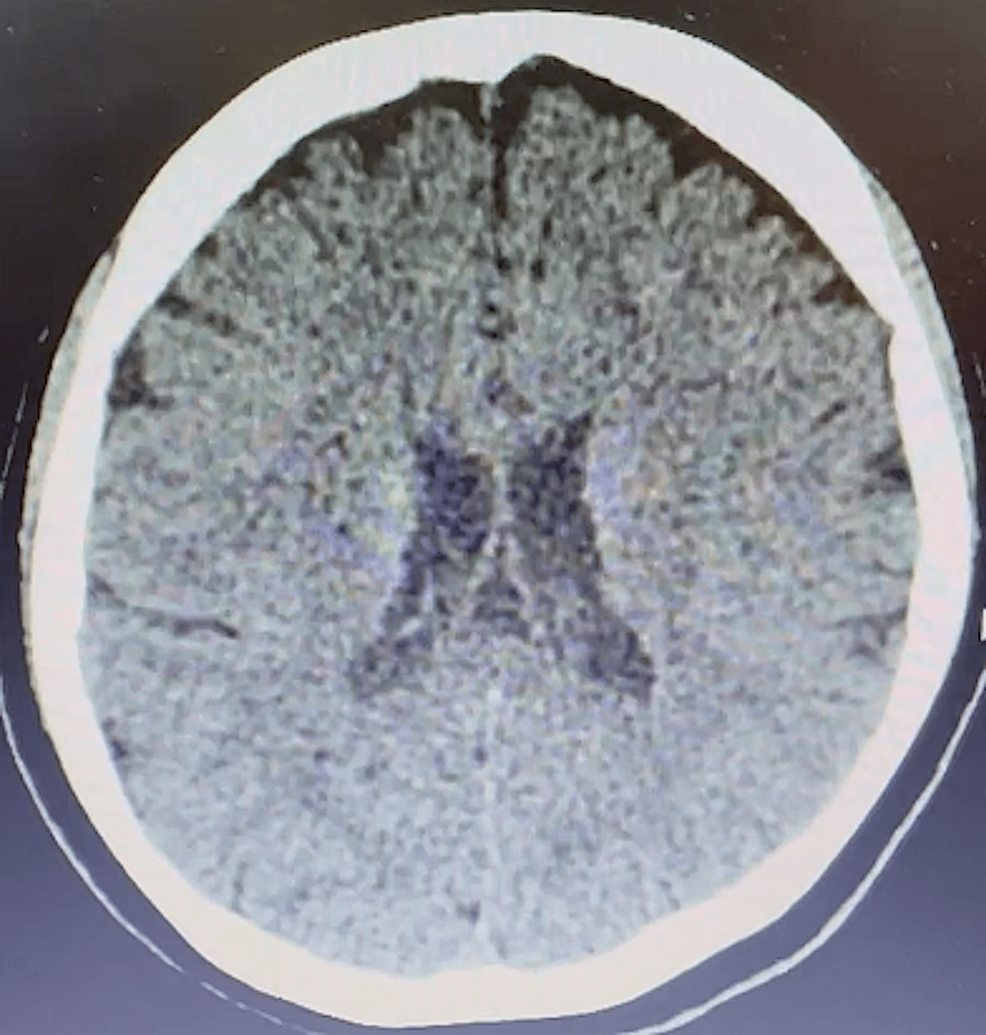

Bilateral Internuclear Ophthalmoplegia Multiple Sclerosis . — many patients with bilateral internuclear ophthalmoplegia consequently show characteristic patterns of disorganised vertical eye. — inflammatory demyelinating lesions, especially occurring in the posterior fossa, result in a wide range of disorders,. — about a third of the cases of internuclear ophthalmoplegia are caused by infarctions and are commonly unilateral and seen in older individuals. — bilateral internuclear ophthalmoplegia in a patient with multiple sclerosis. (a) in primary gaze, the patient has an exotropia.